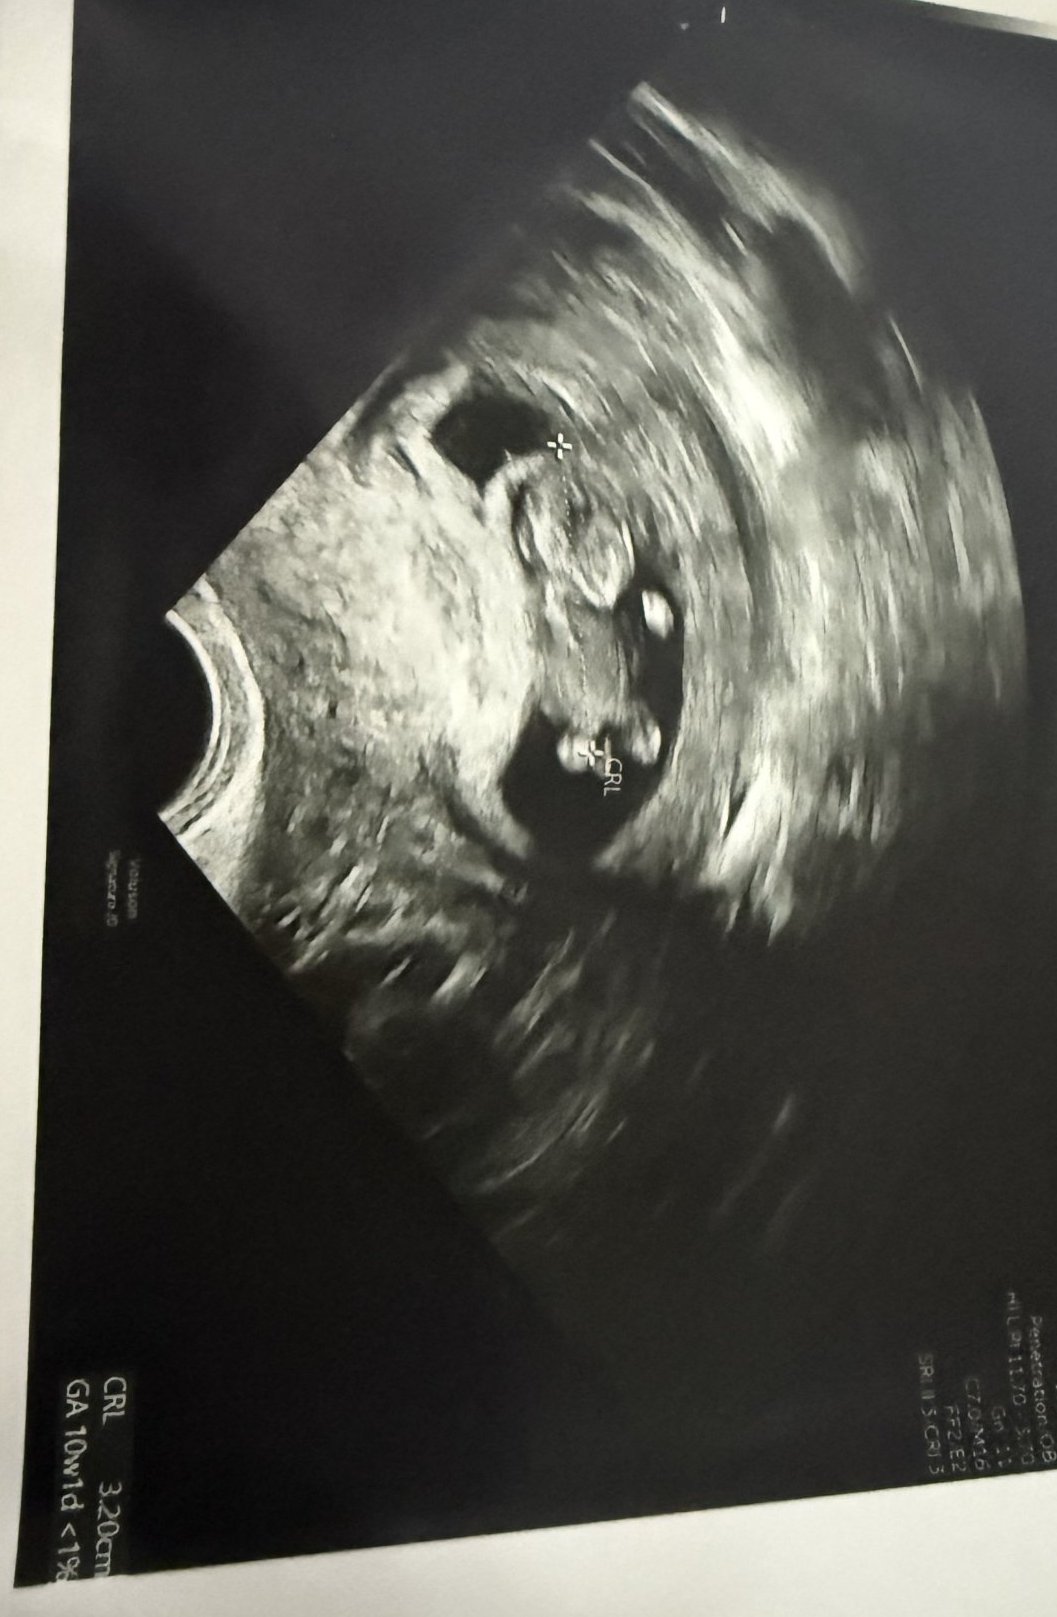

Тази смимка добре ли е за 10 седмица ?

Mareshkahfjjjjsk,добре е,отговаря си за седмицата.